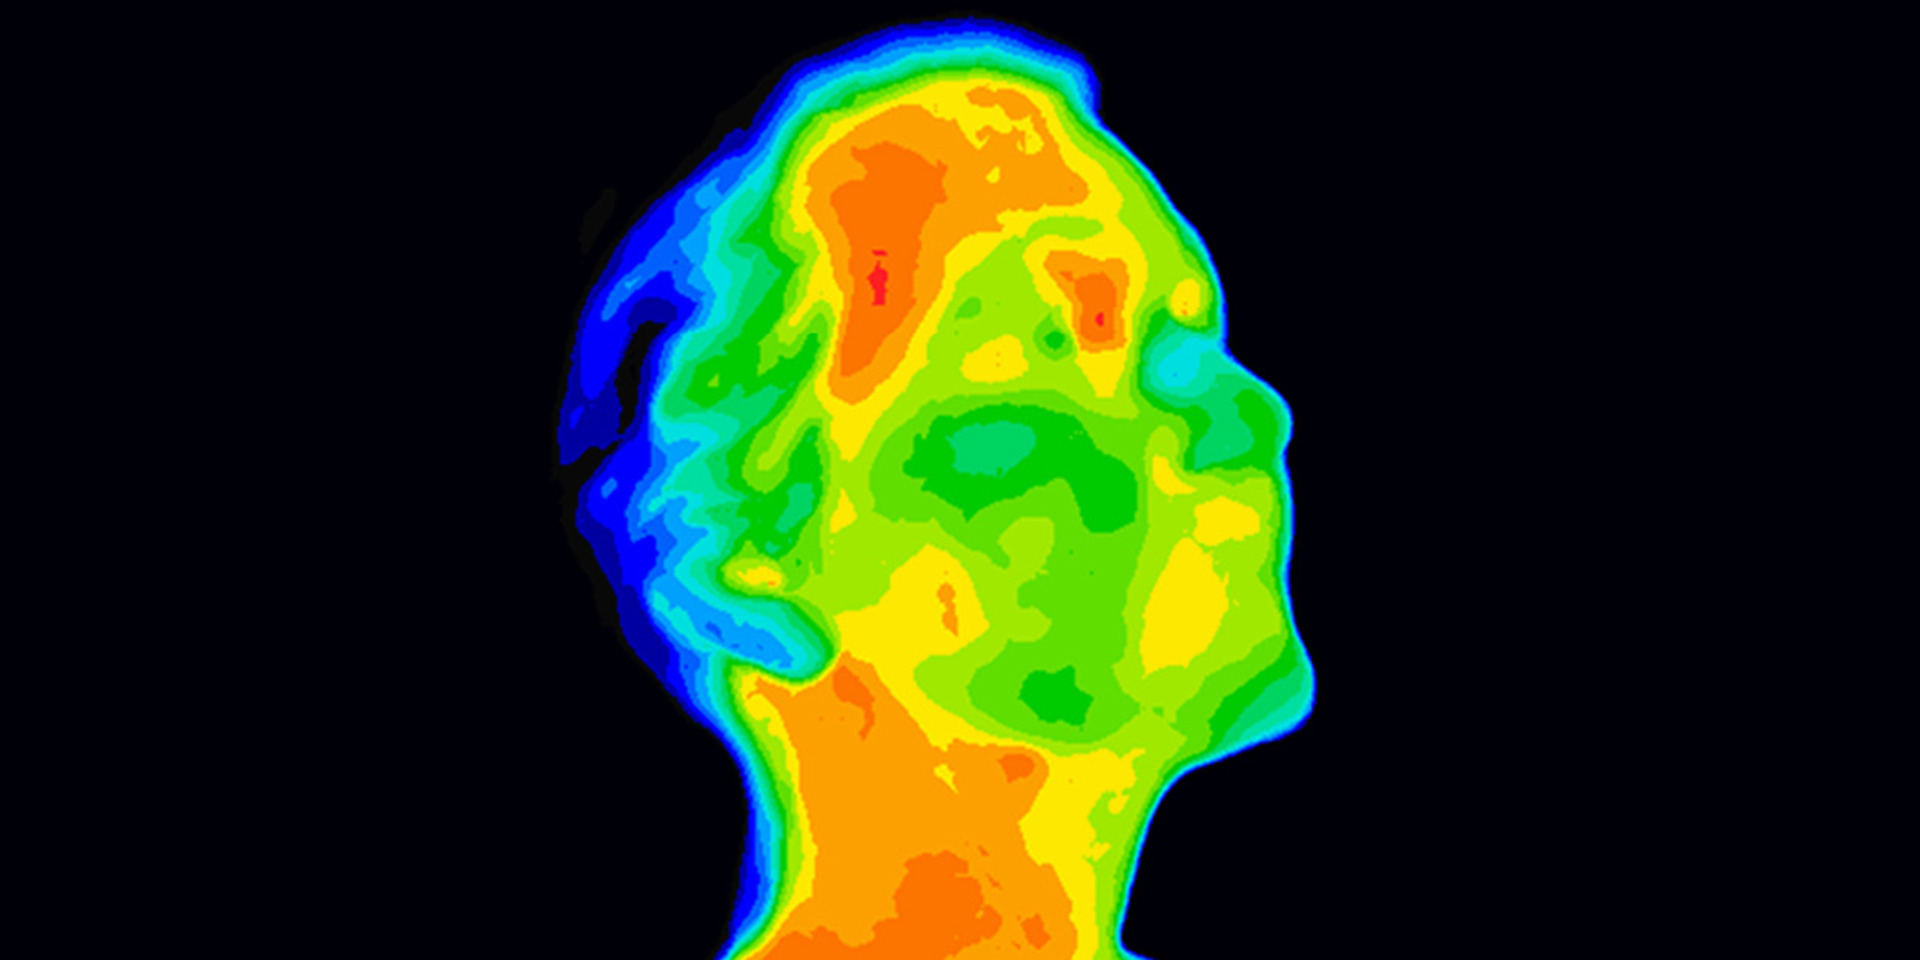

דובר 2: אושרית פאר אני סיימתי דוקטורט בהנדסה ביו-רפואית בתל אביב הנושא של המחקר שלי היה לדימות יתר מרפואי שלמעשה נושא המחקר היה ניטור טיפול קרינתי של מטופלות חולות בסרטן שד בעזרת הדמיה תרמית מה שאני עושה היום אנחנו למעשה מפתחים מערכת של זיהוי קורונה באמצעות צילום של הגב בטלפון סלולרי ע"י חיבור של תוסף של מצלמה תרמית כל זה זה שזו שיטה הזמינה זולה ללא קרינה ללא מגע שמבוססת על זיהוי של החום הנפלט מפני האובייקט הנמדד שבמקרה שלנו זה האור שלנו אני

דובר 1: מסתכל על התמונה התרמית שצילמתם פה ובשוליים ירוק חזי ירוק יותר בעיר צהוב ובמרכז חול למרכז של הגב אדום ורוד גוונים כאלה חמים זה חולה קורונה

דובר 2: זה דווקא נבדק בריא אבל לפילוג הטמפרטורות אתה בדיוק עולה עלה עניין פילוג הטמפרטורות הוא שונה בין אדם בריא לאדם חולה הקשר בין זיהוי חום ללמצב הבריאותי שלנו זה דבר שידוע כבר אלפי שנים עוד היפוקרטס כתב איפה שיש עודף של חום או תחושת קור שם המחלה כדי להתגלות כלומר הקשר הזה הוא קשר הדוק בין הבריאות מצב בריאותי שאנו לחומש שנפלט מהגוף